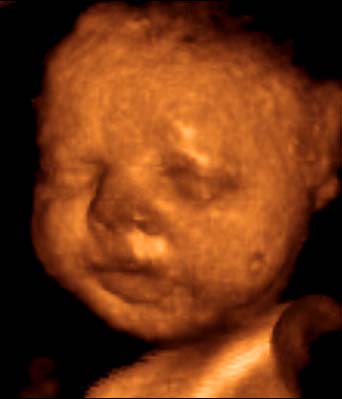

Na megjöttünk a 4d-ről. Hihetetlen élmény volt de tényleg. Még a könnyeim is potyogtak olyan jó volt :lol: Láttuk mindenét tényleg puncis láttam a fülét száját lábait kezeit gerincét. Szopta az ujjacskáját meg a ködökzsinort is bevette a szájába :lol: tünemény folyamatosan mozgott. Takargatta magát az elején mint egy igazi kislány :lol: Van róla dvd meg fotó is szóval csodálatos volt az egész :lol:

Ő nem a mi babánk de ilyen egy 4D uh.

Tényleg nagyon szupi, teljesen látni a babát, nemcsak a körvonalait. :D

Igen és nagyon jól lehetett látni hogy mit csinál :lol: olyan volt mintha átlátszó lett volna a pocak hihihi